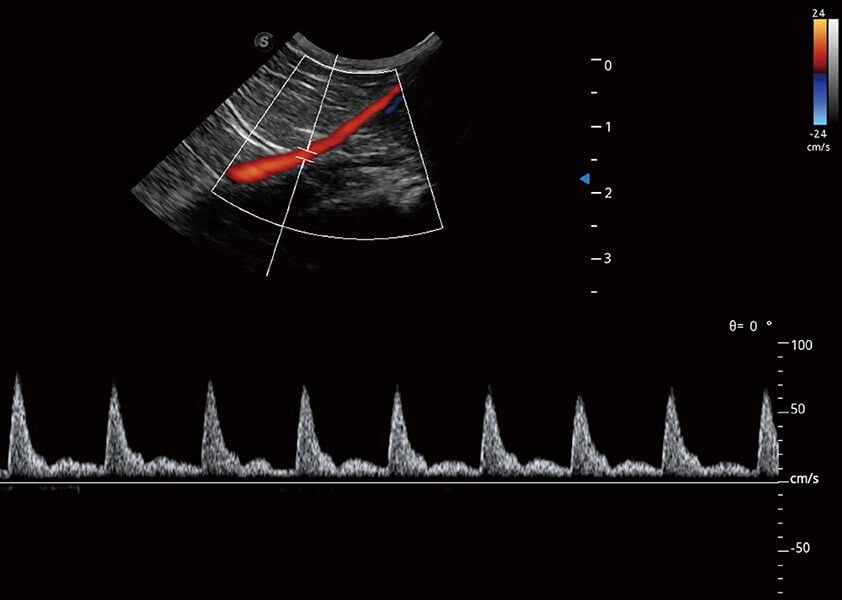

ProPet 60 作为一款高端台式动物超声设备,为动物医生的日常诊断提供了一系列贴合动物临床需求、解决临床实际问题的高级成像功能。凭借全系列高清探头,满足医生对腹部、心脏、生殖、浅表、肌骨等成像的所有需求,切实帮助您提升检查效率,提高诊断信心。

动物是人类最亲密的朋友和最值得信赖的伙伴。云顶集团官网也一直致力于探索动物专用的超声影像解决方案。 全新推出的ProPet系列,是云顶集团官网在动物超声影像智能化、专业化、精准化的一次跨越式革新。动物不能用言语来表述自己的不适,通过超声影像,ProPet系列搭建了动物医生与不同物种沟通的“桥梁”,为动物医生注入了“治愈之力”。